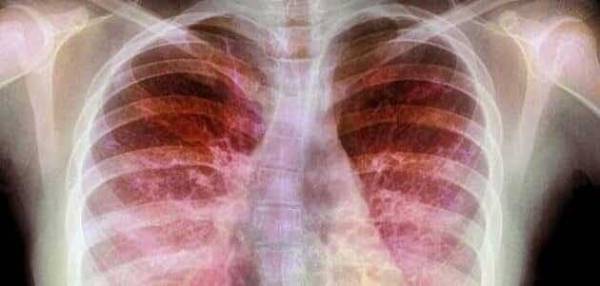

طبيب باطني مختص في الأمراض الباطنية ويحمل البورد الأردني في هذا الإختصاص يقوم ومن خلال عيادته والمستشفى الخاص الذي يتعامل معه ويستدعيه في بعض الحالات بتسويق نفسه على أنه طبيب مختص في الأمراض الصدرية دون أن يحمل بورد أردني في هذا الإختصاص .

الطبيب يمارس اختصاص الأمراض الصدرية لمدة عشرون عاماً في المملكة دون أن يحصل على شهادة البورد الأردني في الأمراض الصدرية من المجلس الطبي الأردني .

هذا التجاوز وهذه المخالفة يجب على وزير الصحة فراس الهواري "المختص بالأمراض الصدرية" أن يوقفها ويحاسب بشكل جازم وصارم جميع من سمحوا لأنفسهم بممارسة معالجة المواطنين داخل أراضي المملكة وفي عياداتهم الخاصة وفي أقسام العناية المركزة في بعض المستشفيات عبر تلك السنين الطويلة دون أن يعملوا بالأنظمة والقوانين التي تلزمهم بضرورة حصولهم على البورد الأردني في تلك الإختصاصات .